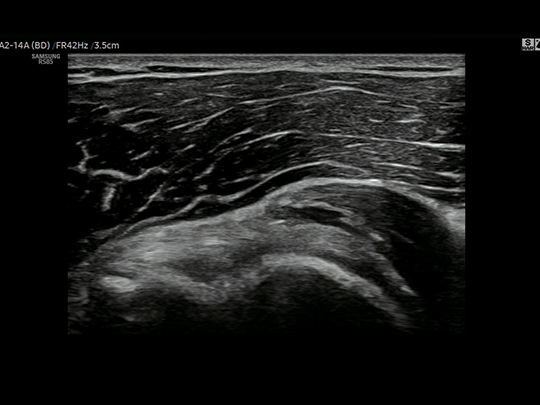

WideScreen provides approximately 23% more lateral viewing information compared to normal screen, allowing ultrasonic examination with wider view at a glance.